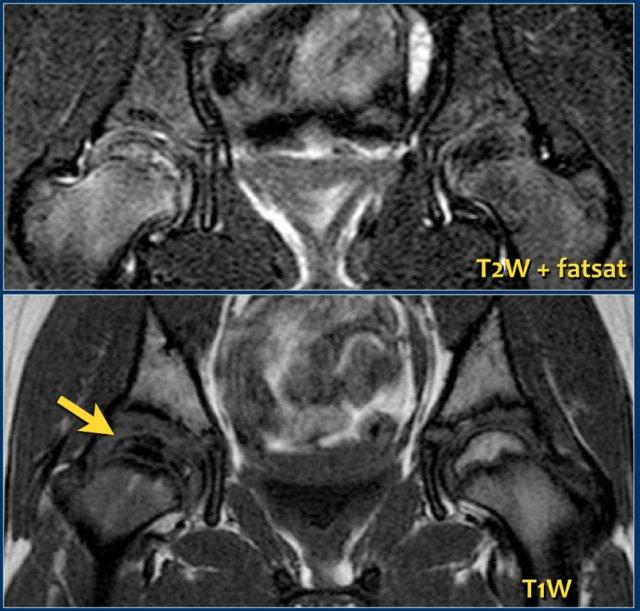

VKN thiếu niên tự phát: Tràn dịch khớp háng phải trong JIA. Màng hoạt dịch dày lên và ngấm thuốc tương phản từ Gadolinium (phải). Hình ảnh do Bác sĩ LS Ording Muller cung cấp

Viêm Khớp Tự Phát Thiếu Niên

Viêm khớp tự phát thiếu niên (JIA) là một chẩn đoán lâm sàng và hiện được phân thành sáu phân nhóm khác nhau.

Trong hầu hết các trường hợp, ít hơn 4 khớp bị ảnh hưởng. Các khớp lớn chủ yếu bị tổn thương, bao gồm khớp háng.

JIA khởi phát bằng viêm bao gân và chỉ sau đó mới biểu hiện phù nề xương, viêm màng xương, loãng xương và rối loạn tăng trưởng.

Trái với người lớn, mất sụn khớp và bào mòn xương không phải là dấu hiệu thường gặp trong JIA.

Phim X-quang thường âm tính ở giai đoạn sớm của bệnh.

Siêu âm sẽ cho thấy tràn dịch, màng hoạt dịch dày và đôi khi tăng sinh mạch máu.

MRI cũng có thể phát hiện tràn dịch khớp và dày màng hoạt dịch, đồng thời có thể đánh giá tổn thương xương và sụn.

Đây cũng là phương thức hình ảnh tốt để đánh giá các rối loạn tăng trưởng do bệnh gây ra.